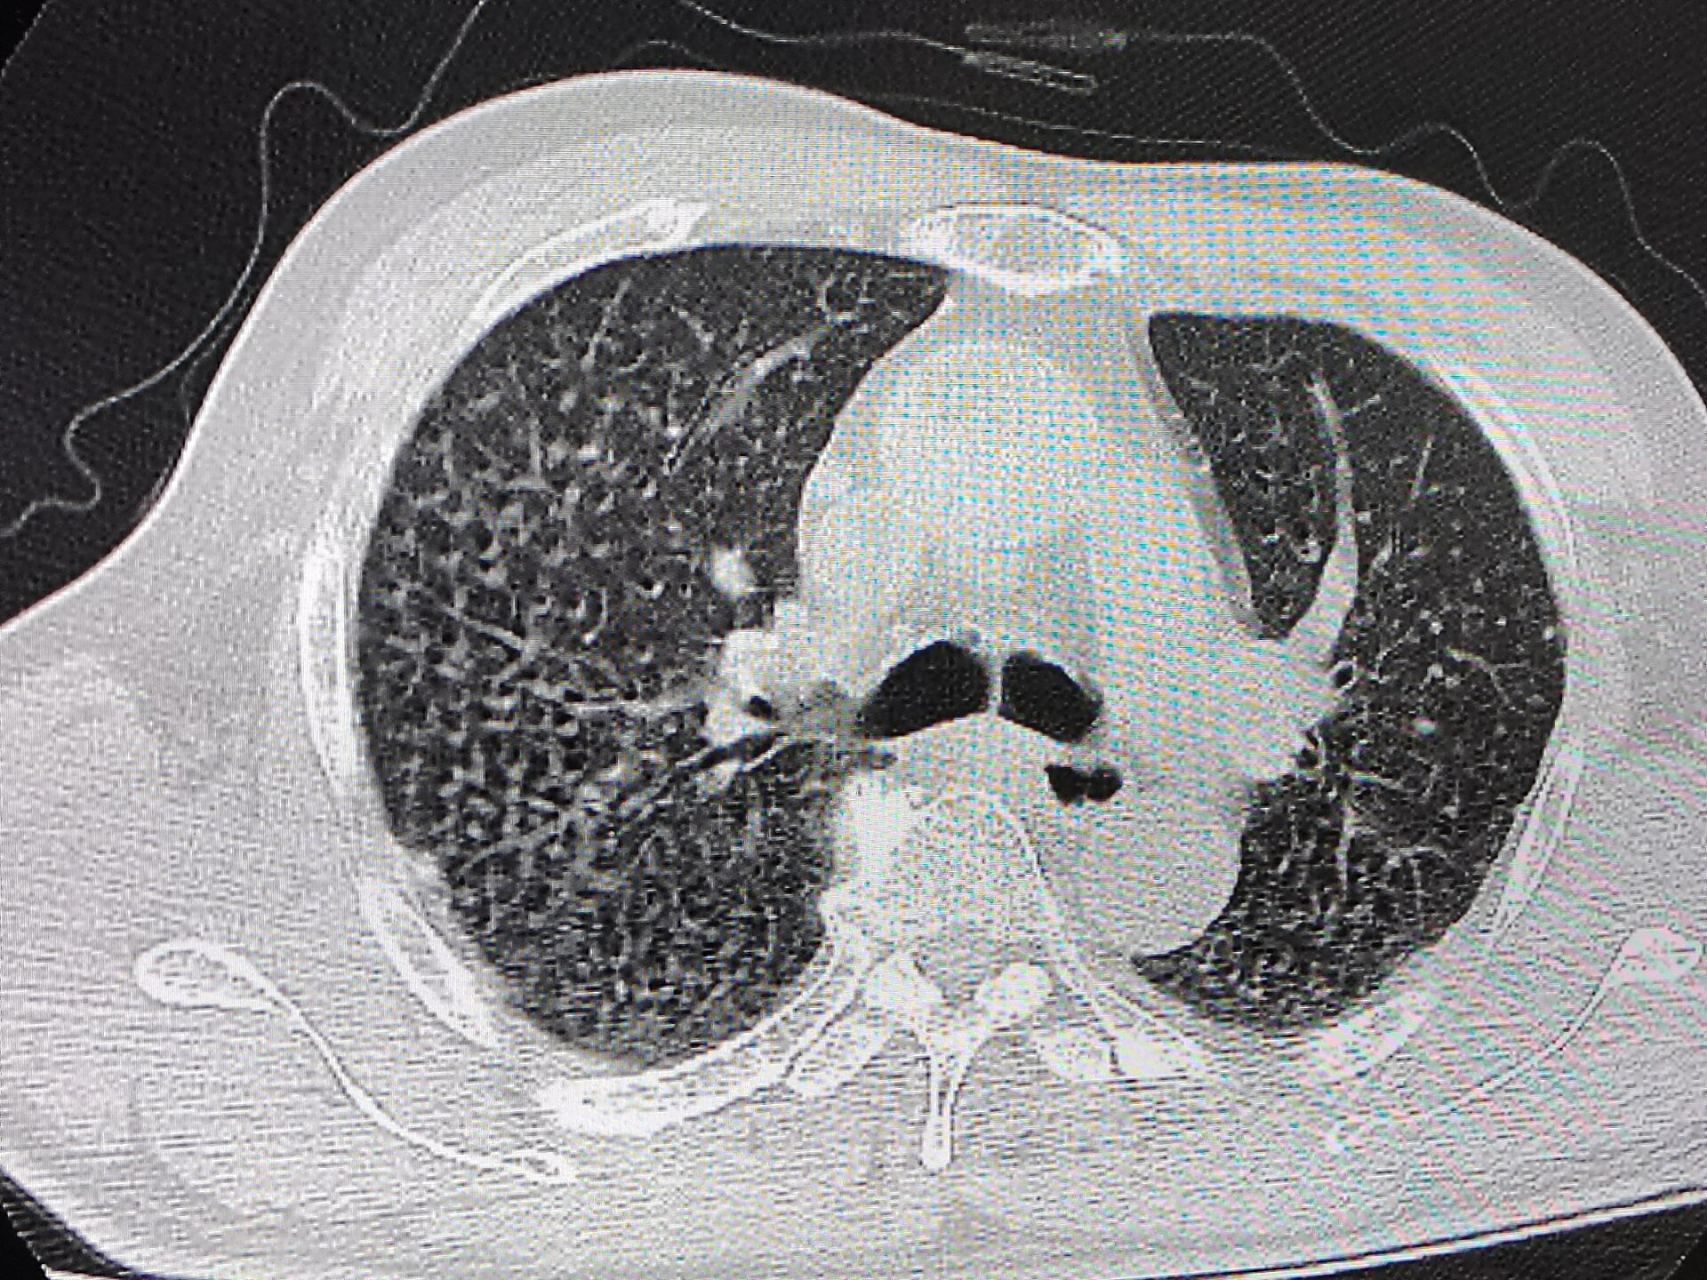

矽肺ct表现 两肺见弥漫多发粟粒结节影,可以看到两肺门,纵隔淋巴结轻

早期矽肺ct特征表现为双肺多发,无融合的小结节影,大小不等,多为2